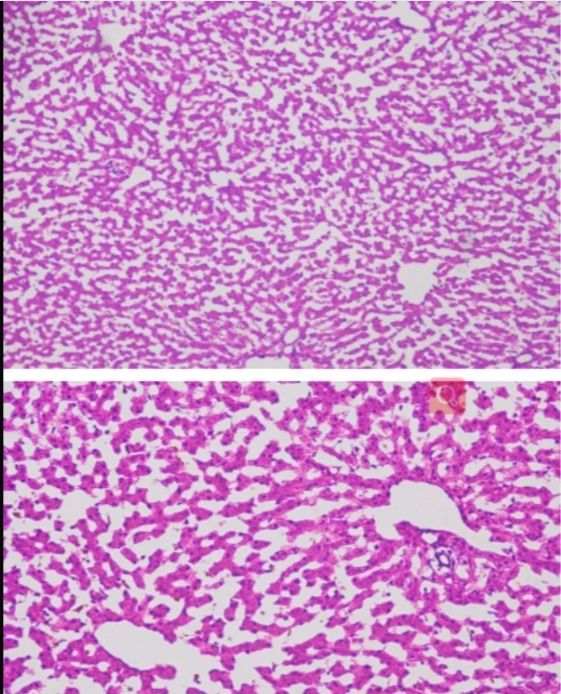

今天普拉特澤生物繼續(xù)跟大家一起學(xué)習(xí)新的實(shí)驗(yàn)——冰凍切片,是一種重要的實(shí)驗(yàn)技術(shù),它在低溫條件下使組織快速冷卻到一定硬度,然后進(jìn)行切片。這種技術(shù)具有簡(jiǎn)便、快速、組織變化小以及能夠保存脂肪和類脂等成分的優(yōu)點(diǎn),被廣泛應(yīng)用于生物學(xué)、醫(yī)學(xué)等領(lǐng)域。本文將詳細(xì)介紹冰凍切片實(shí)驗(yàn)的原理以及其在各個(gè)領(lǐng)域的應(yīng)用。 冰凍切片實(shí)驗(yàn)原理以及應(yīng)用由普拉特澤生物組織染色檢測(cè)平臺(tái)總結(jié)分享,組織染色檢測(cè)平臺(tái)為廣大科研實(shí)驗(yàn)人員提供冰凍切片外包實(shí)驗(yàn)服務(wù),先一起來學(xué)習(xí)學(xué)習(xí)什么是冰凍切片~

冰凍切片實(shí)驗(yàn)的原理基于低溫下組織的物理性質(zhì)變化。在冷凍狀態(tài)下,組織內(nèi)的水分形成冰晶,使組織變得堅(jiān)硬而易于切片。這種切片方法不需要對(duì)組織進(jìn)行固定、脫水、透明、包埋等繁瑣步驟,因此大大縮短了制片時(shí)間。同時(shí),由于避免了化學(xué)處理或加熱過程,冰凍切片能更好地保存組織的原始結(jié)構(gòu)和成分,特別是對(duì)于那些對(duì)有機(jī)溶劑或熱敏感的細(xì)胞表面抗原和水解酶。

冰凍切片在病理學(xué)診斷中具有重要應(yīng)用價(jià)值。通過冰凍切片技術(shù),病理醫(yī)生可以快速獲取組織樣本的切片,進(jìn)行顯微鏡下觀察和分析。這有助于醫(yī)生在術(shù)中快速判斷腫瘤的性質(zhì)、淋巴結(jié)是否有轉(zhuǎn)移等關(guān)鍵信息,從而指導(dǎo)手術(shù)范圍和后續(xù)治療方案。

冰凍切片還可以用于免疫組化研究。通過冰凍切片技術(shù),研究人員可以制備含有特定抗原的組織切片,進(jìn)而利用免疫組化方法檢測(cè)和分析抗原的表達(dá)情況。這對(duì)于研究細(xì)胞的生物學(xué)功能、疾病的發(fā)生機(jī)制以及藥物的療效評(píng)價(jià)具有重要意義。

由于冰凍切片能夠較好地保存組織的化學(xué)成分,因此也適用于組織化學(xué)分析。例如,研究人員可以利用冰凍切片技術(shù)制備含有特定酶類或代謝產(chǎn)物的組織切片,進(jìn)而進(jìn)行酶活性測(cè)定、代謝產(chǎn)物檢測(cè)等分析。這有助于揭示組織的代謝途徑、功能狀態(tài)以及與疾病的關(guān)系。